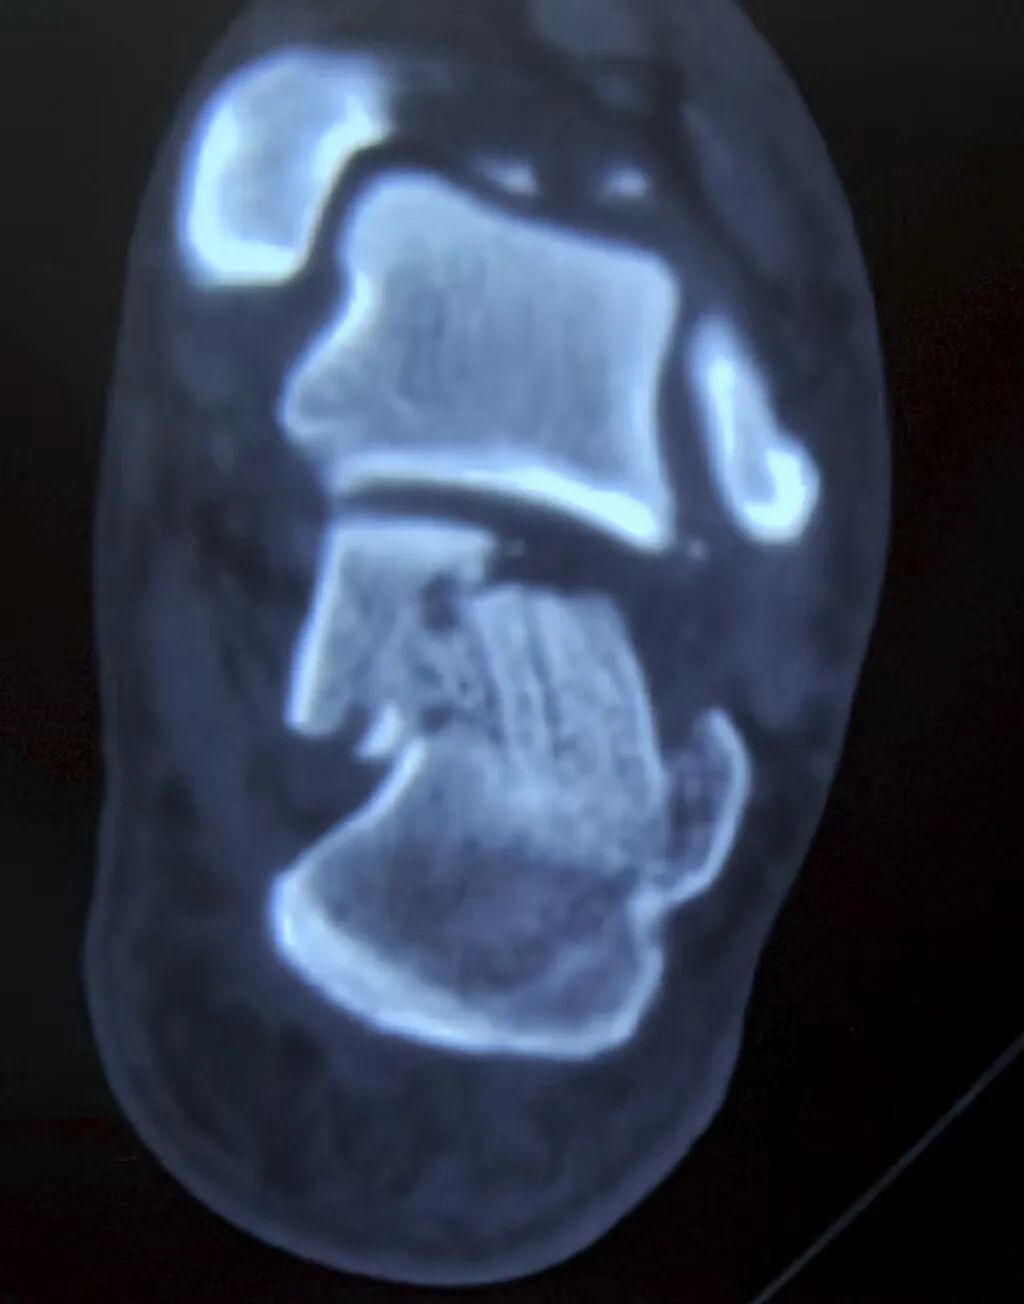

术前对骨折块以及骨折线的方向的了解是非常重要的,CT是很好的工具。

CT可以很好的显示嵌插骨块的位置(这个对复位至关重要)

这是一例比较复杂的跟骨,合并舌型骨折块,同时内侧嵌插严重,关节面塌陷。